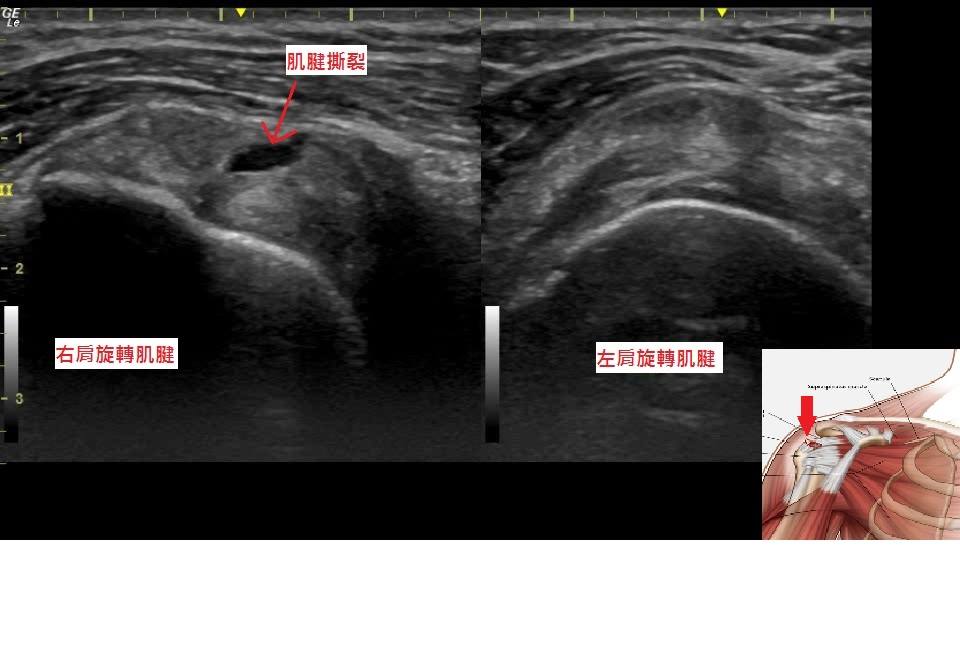

肩痛半年的患者,一直以為是五十肩,結果超音波下發現是旋轉肌腱撕裂傷。

【圖1&2】肩痛的患者,超音波可以協助診斷肩關節問題及輔助醫師精準注射。